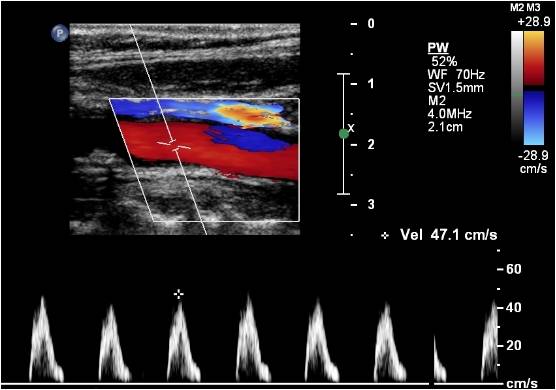

The diagnosis of carotid artery occlusion is made by vascular imaging. Duplex ultrasound can show absence of flow. The duplex can show thrombus in the artery and absence of flow with pulse wave and color Doppler. A clue to the diagnosis is the waveform in the common carotid artery. It becomes more high resistance than usual: